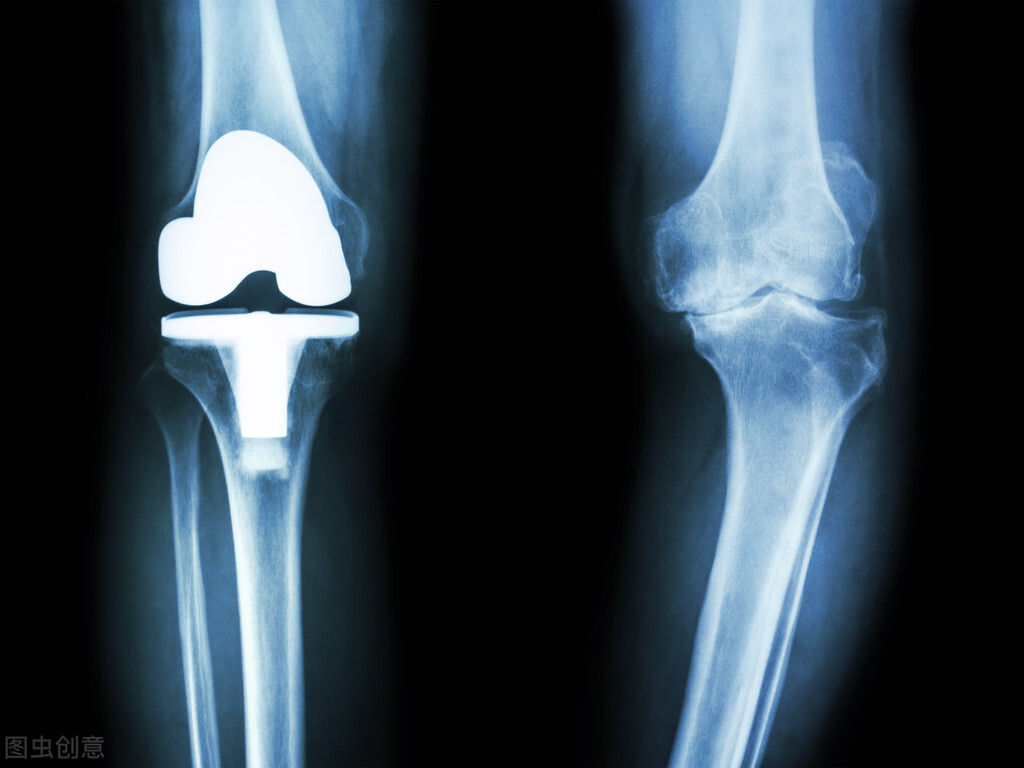

04 / 关节置换术

如果患者的病变到了晚期,出现关节畸形,明显影响生理功能,经保守治疗无效后,则要考虑人工关节置换术,主要适用于膝、髋关节。

类风湿关节炎以手足小关节受累居多,但膝、髋关节受累也比较常见,而这两个关节直接关系到人体的站立和行走功能。对于晚期患者,关节间隙消失或明显狭窄,关节软骨及软骨下骨破坏严重,关节功能严重丧失,可造成残疾,患者只能卧床不起,这时候为了避免长期卧床带来的副作用,患者就要考虑置换人工关节。

人工关节置换术是治疗关节病的终极手段,合理应用可以让关节“起死回生”,而且随着材料、设计和手术的不断改进,现在人工关节的寿命和手术成功率都很有保障,术后可以有效消除疼痛症状和改善患者的日常活动能力,提高生活质量。

终末期类风湿患者要考虑置换人工关节